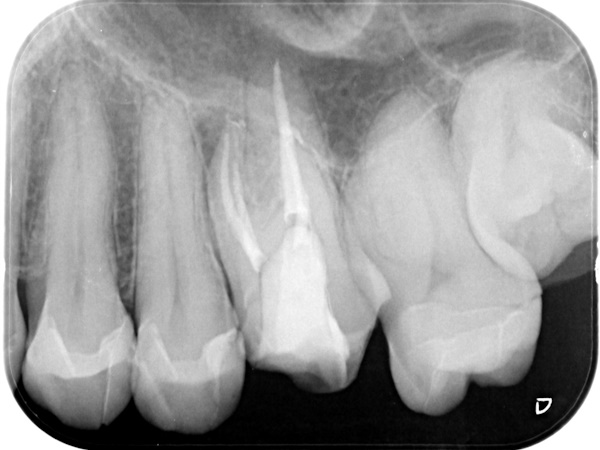

根管治療終了時